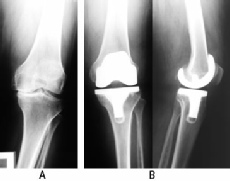

Joints that are severely injured by trauma or that have degenerated significantly may need to be replaced.

There are many types of joint replacement. Anyone having a joint replacement will need some rehabilitation. The protocol for this will depend on a wide range of factors, including

Some prehabilitation may be indicated to prepare a patient physically for the surgery. This may include an exercise programme to maximise muscle strength and available range of movement, maximise balance and co-ordination, to learn the post operative exercise programme and to ensure good respiratory function.

The rehabilitation following a joint replacement will include basic exercises within 24 hours of surgery and progressively more active exercise during the days after the operation to restore muscle activity and function as quickly as possible.

For joints replaced in the lower limbs this will include getting back on the feet and walking with ‘normal’ gait as soon as possible.

Special attention may be paid to some muscle groups known to be affected adversely by either the deterioration of the joint / the surgery or by special risks – such as possible dislocation of the joints.

In lower limb joint replacement the important muscle groups for rehab will be the hip extensors and abductors, the knee extensors and flexors and the calf muscles. The key functional activities are walking, step climbing and getting up / down from standing to sitting.